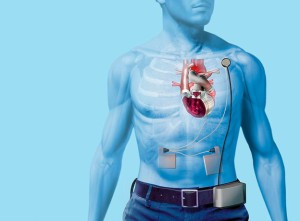

Na kalifornské univerzitě vyvinuli umělé srdce určené k testování léků

Bioinženýr Kevin Healy a jeho kolegové z kalifornské univerzity vyvinuli silikonové platformy porostlé sítí buněk lidské srdeční svaloviny. Získali tak funkční model lidské srdeční tkáně použitelný jako nástroj pro testování nových léků na srdce a oběhovou soustavu.

Nový orgán představuje zajímavý milník ve vývoji rychlejších metod testování toxicity nově vyvíjených léků. Projekt lidského srdce financovala Tissue Chip for Drug Screening Initiative, mezinárodní iniciativa založená vládní americkou vládní agenturou National Institutes of Health (NIH), za účelem vývoje čipů se 3D lidskými tkáněmi.

Healy uvedl, že při používání zvířecích modelů v testování léků dochází k velkému počtu omylů a že zvířecí modely nejsou ve zjišťování účinků nových léků na lidi zcela spolehlivé. Testy nových léků na lidech bývají zase eticky problematické, ale modely lidských tkání a orgánů by tento nepříznivý stav mohly zvrátit.